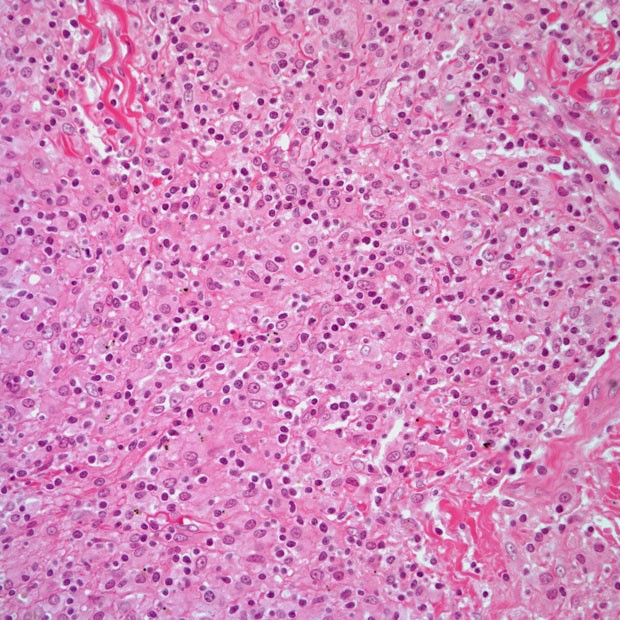

图说 ▍非霍奇金淋巴瘤(下篇)

620x620 - 160KB - JPEG

620x620 - 167KB - JPEG